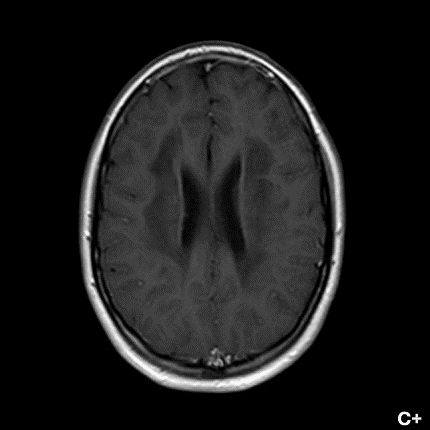

- B) Kontrastsız T1A serilerde tarifli alanlarda hipointens (oklar) görünüm izlendi. Kontrastlı T1A serilerde bu düzeyde (oklar) kontrastlanma artışı izlenmedi. Diffüzyon ağırlıklı serilerde belirgin diffüzyon kısıtlaması (oklar) görülmedi.

- Etkilenen bölgelerde T1’de hipointens, T2/FLAIR’da hiperintens sinyal değişiklikleri izlenir. DWI’de lezyonların periferinde kısıtlı difüzyon görülebilir. MRS’de beyaz cevherde laktat artışı saptanabilir, ancak bu her hastada mevcut değildir.